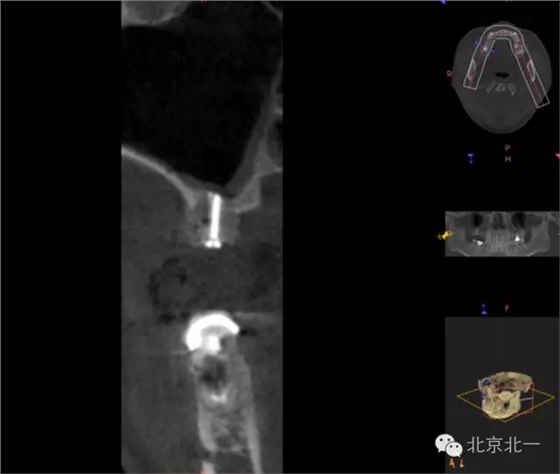

CBCT顯示,骨寬度可,骨高度不足,月3mm。頜間距離增大。

圖三:骨高度3mm.

圖十八:手術前CBCT

圖十九:手術后當天CBCT

圖二十-二十二:ONLAY植骨半年后